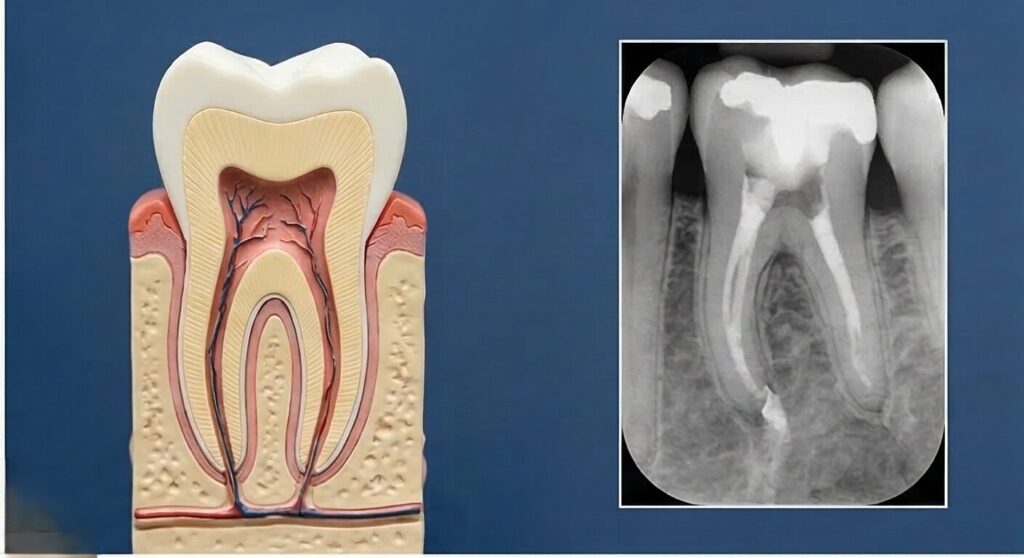

根管治療は、歯の内部にある神経や感染した組織を除去し、きれいにした上で薬を詰める治療です。

理由の一つは、歯の根(根管)の構造がとても複雑だということです。

根管は1本の歯に1本とは限らず、3本、4本ある場合もあります。

さらに根管が途中で枝分かれしていたり、極端に曲がっていたりすると、すべての部位にアプローチするのに回数を要します。